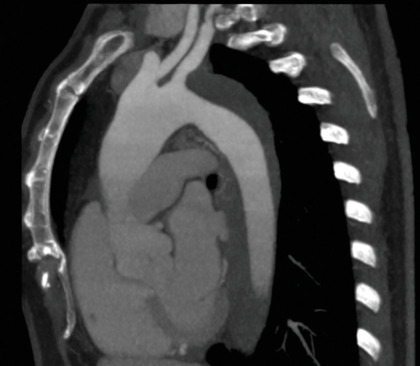

Aortic intramural hematoma (IMH) accounts for approximately 10%-25% of acute aortic syndromes (AAS), and multi-slice computed tomography and magnetic resonance imaging are the leading techniques for diagnosis and classification. In this context, endovascular strategies provide a valid alternative to traditional open surgery and transesophageal echocardiography (TEE) could play a role in therapeutic decision-making and in endovascular repair procedure guidance. A 57-year-old female patient with IMH extending from the left subclavian artery to the upper tract of the abdominal aorta, underwent endovascular aortic repair using an unibody single-branched stent grafting in the aortic arch and descending aorta with a side branch inserted in the left common carotid artery. To restore proper flow in the left axillary artery, a carotid-subclavian bypass graft was performed. The procedure was guided by angiography and TEE. Intraoperative TEE revealed aortic IMH with a significant fluid component in the middle tunic of the aorta with a wall thickness of over 13 mm. TEE was useful in monitoring of all steps of the procedure, showing the presence of the guidewires into the true lumen, the advancement of the prosthesis, and the phases of release and anchoring. This case highlights the importance of using multimodality imaging techniques to evaluate AAS and demonstrates the growing potential of TEE in guiding endovascular repairs.